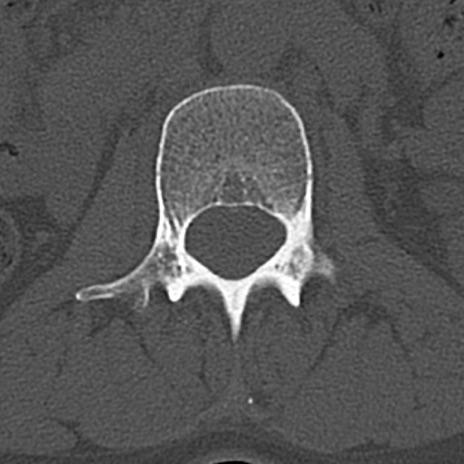

【整形】TIPS症例4 腰椎CT(横断像)

腰椎CT

横断像と矢状断像